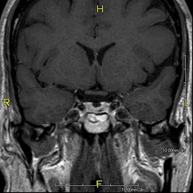

- RM Cerebral (craneal)

Prueba diagnóstica no invasiva que consiste en la obtención de imágenes de alta definición anatómica del cerebro mediante el empleo de un campo electromagnético y ondas de radio (con un emisor y un receptor). No utiliza radiación ionizante. Indicaciones: problemas vasculares, pérdida de memoria, epilepsia, cefalea, malformaciones, sospecha de tumor, meningitis. - RM Cais